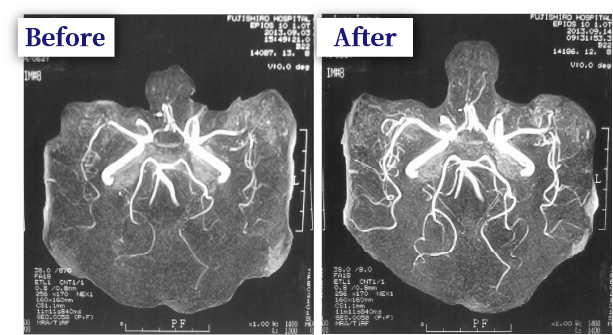

MRI and MRA are used to examine the brain itself and MRA to check the blood vessels.

The MRI and MRA are used to determine what diseases are present in the brain, which parts of the brain are damaged, and which blood vessels are affected.

Here are some of the main MRA images. The MRA images can be used as a reference to determine which parts of the cerebral blood vessels are clogged or stenosed, and to make changes in the brain that may result from treatment.

First of all, the MRA image shows what the arteries in the brain look like in the picture on the P-wing.

Normal human cerebral blood vessels

Cerebral vessels with stenosis

Don’t overlook the signs of cerebral infarction!

The shining white lines are blood vessels through which blood flows. If the white lines are connected as shown in the picture, the blood vessels are normal, but where stenosis has occurred, the areas that were white have become lighter or black. If a cerebral infarction occurs, there is no blood flow beyond that point, so the blood vessels do not show up.

By not overlooking these signs of stroke and starting treatment before the disease occurs, the risk can be avoided.

Example of treatment 69 years old male, Mr. A

He has lower extremity pain while walking and sometimes falls over due to dizziness.

He has started to feel a slight tremor in his hands.

MRA showed bilateral middle cerebral artery stenosis and ischemic foci in the posterior cerebral artery. The patient was treated with intravenous infusion. After 10 days of intravenous infusion, the stenosis of the arterial vessels improved markedly and the patient's complaints almost disappeared.

Example of treatment 70 years old male, Mr. B

Example of improvement after stroke. Patient with right hemiparesis, dizziness and gait disturbance. MRA of the brain showed

The left middle cerebral artery is occluded, the left middle cerebral artery is stenotic, and the right posterior aorta is ischemic.

An example of a partially occluded area of an artery after stroke. After the same intravenous treatment as above. The occlusion of the left middle cerebral artery did not improve, but the stenosis of the other arteries improved markedly, and the patient's physical condition clearly improved.

The dead brain cells beyond the stroke site are not changed,

However, the narrowing of the area outside of the occlusion site is improved, and the symptoms of the brain beyond the occlusion site are restored.